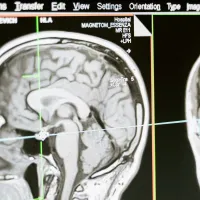

Interdisciplinary Dementia and Ageing Centre

We are a network that brings together local expertise from across the research spectrum within the University and University Hospital Southampton. Our aim is to increase understanding of dementia and brain ageing and how to treat and care for people with these conditions. -

Neuroscience

We work on national and global priorities of health and well-being, underpinning research in neuroscience, and age-related neurodegenerative diseases, including Alzheimer’s. -

Southampton Imaging

Imaging has become an essential part of scientific research, from biomedical sciences to engineering to optoelectronics.